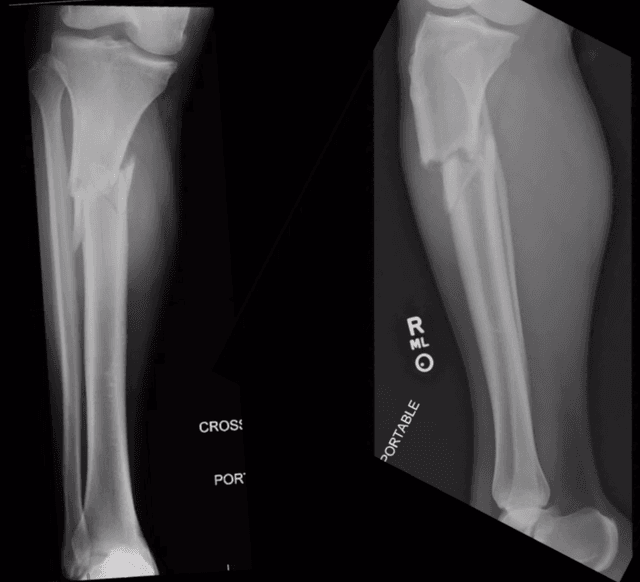

Imaging

Pre-op